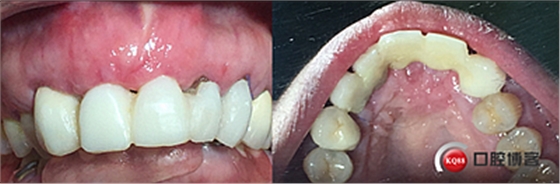

戴牙。

戴牙后半年復(fù)查。